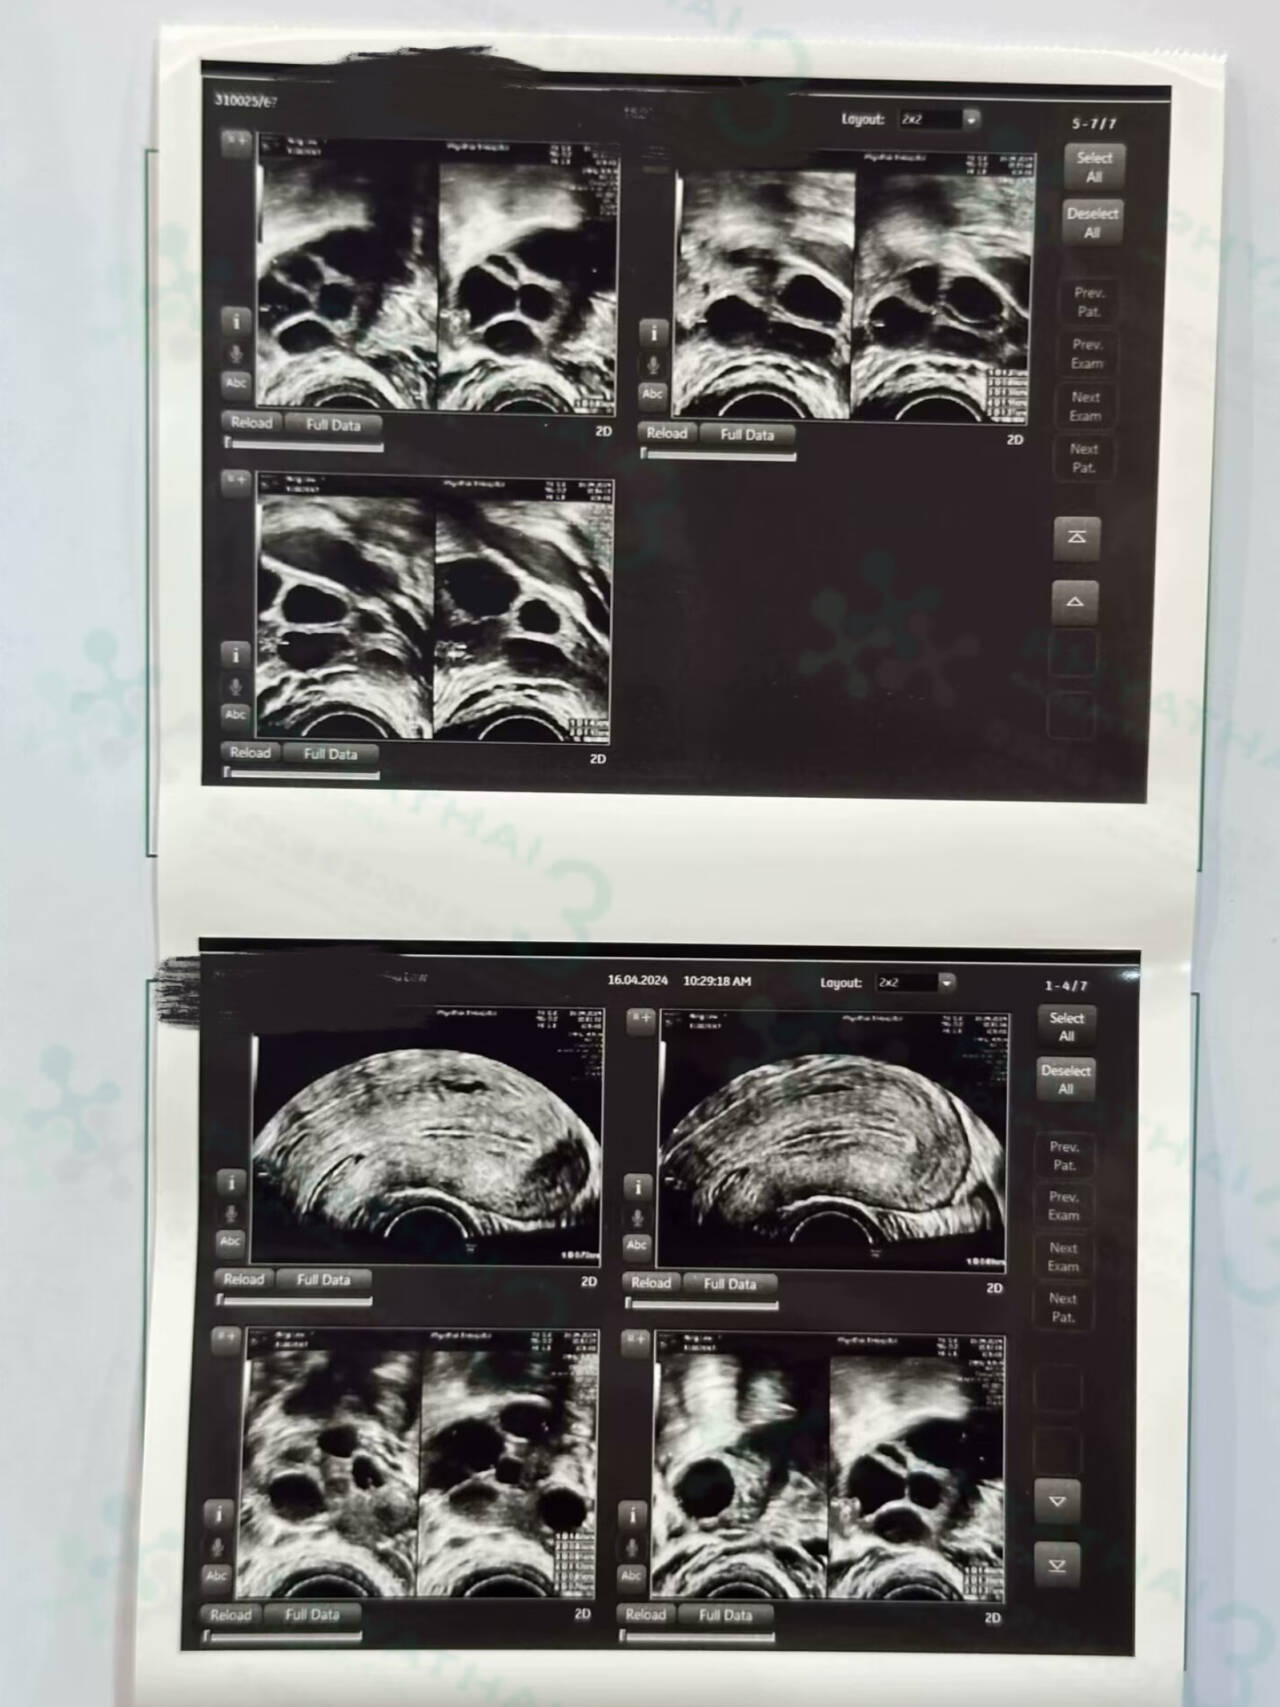

女士去年检测AMH时就看到有卵巢功能衰退了,所以她们决定来帕3进行试管,上次医生让我们先打针4天,今天就一起来看我们的小泡泡发育如何,打针了卵泡对药吸收好不好,复诊的时候M医生也再仔细检查和给女士调理促排方案,为了争取最多能用的卵泡,一起慢慢往前走 加油噢